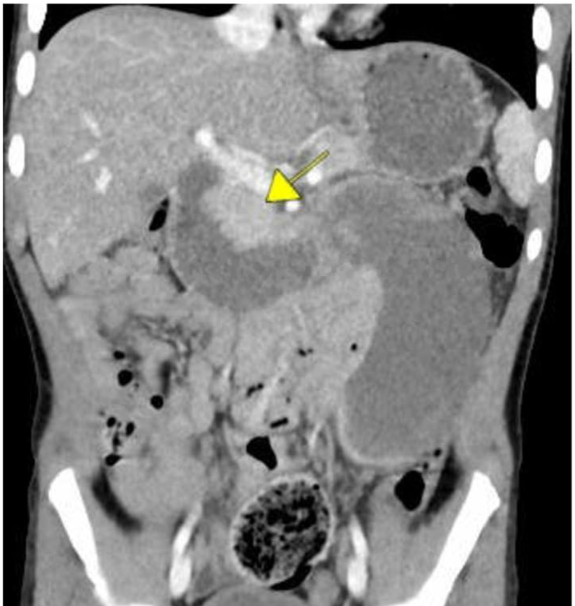

This 5-year single-center study from 2018 to 2022 identified a total of 13 patients with duodenal hematoma (DH). There were a total of 21,569 EGDs, and 16,978 EGDs with duodenal biopsies were performed during the study period.

- 1 DH in 1306 (0.08%) EGDs with duodenal biopsies. Ten of the thirteen patients had normal duodenal histology, and the other three each had findings of celiac disease, peptic duodenitis, and graft-versus host disease

- Symptom onset occurred within 24 h for 8/13 (62%),48 h for 11/13 (85%), and 72 h for all 13 patients after EGD. Emesis occurred in all 13 patients and abdominal pain 7/13 (58%)

- All patients were admitted with a mean length of stay of 18 days

- Treatment: jejunal feedings in 4 of the 13 patients (31%), and parenteral nutrition in 10 of 13 (77%) patients. Most patients (62%) utilized opioids for pain management following DH